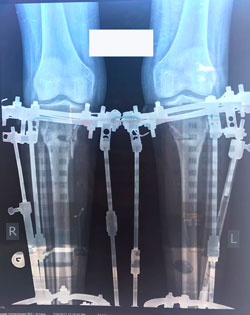

Исходник - 19 лет.

Дата операции 25.05.2017г.

В процессе круток

58 дней.

Через 2 недели можно на снятие аппаратов.

Срок лечения 75 дней.